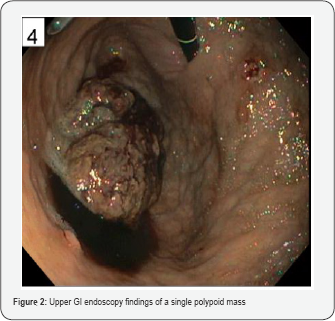

The patient was a 55-year-old Hispanic man who presented with anemia (hemoglobin (Hg) 7.6g/dL, hematocrit (Hct) 26%), epigastric abdominal pain, and melena. The patient had these symptoms for the past couple of months and they worsened 5 days prior to admission. His past medical history included hyperlipidemia and type 2 diabetes mellitus. On physical exam, he had a soft abdomen that was tender in the epigastric area, and had normal bowel sounds. On CT scan, an increased soft tissue density was identified in the proximal portion of the stomach (Figure 1). No other abnormality within the abdomen was found. Laboratory tests were unremarkable except for low hemoglobin and hematocrit. Preoperative serum tumor markers, such as alpha-fetoprotein (AFP), beta human chorionic gonadotropin (β-hCG), carcinoembryonic antigen (CEA), or lactic dehydrogenase (LDH) were not evaluated. Upper gastrointestinal endoscopy showed a polypoid mass (Figure 2). Due to continued bleeding, surgery was considered necessary and a was performed. H&E and immunohistochemical (IHC) stainings, including desmin (Ventana, Tucson, Arizona), MyoD1 (Cell Marque, Rocklin, California), neurofilament (Ventana, Tucson, Arizona), SALL-4 (Biocare Medical, Concord, California), and synaptophysin (Ventana, Tucson, Arizona), were performed